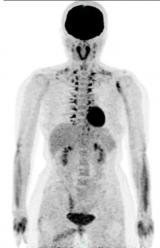

PET/CT显像中的假象——棕色脂肪显影

传统影像学检查(如CT、超声、MRI等)无法区分这两种脂肪,但PET/CT显像可以做到。在18F-FDG PET/CT显像中有约2.3-4%的患者的棕色脂肪可以摄取显影,其中以儿童和女性多见。 2023-02-02 PET/CT放射诊疗辐射成像

PET/CT检查报告里的SUV值是什么?

看到了一个很小的结节,直径只有0.5cm左右,CT上可能都发现不了,但是PET/CT显示其SUV值很高(通俗的说看起来很亮),那就考虑是恶性的,CT有可能就会漏诊了。 2023-02-01 PET/CT